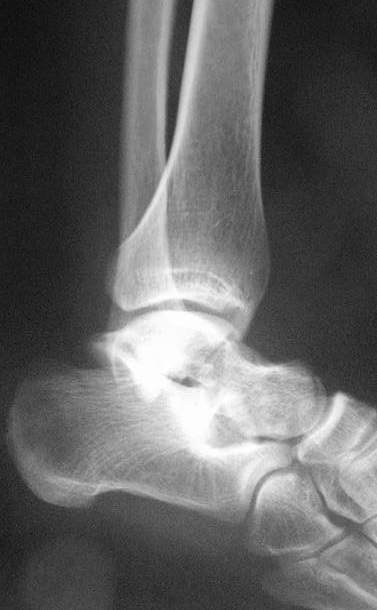

Здесь на фото примеры:

Переломовывих тарана с повреждением медиальной стороны. Через 4 часа после поступления проведена репозиция и фиксация тарана после Irrigation&Debridment. Частичное несращение медиальной лодыжки не беспокоит, вернулся к активному образу жизни. Полная нагрузка разрешена через 11 недель. Финальные снимки через 11 месяцев.